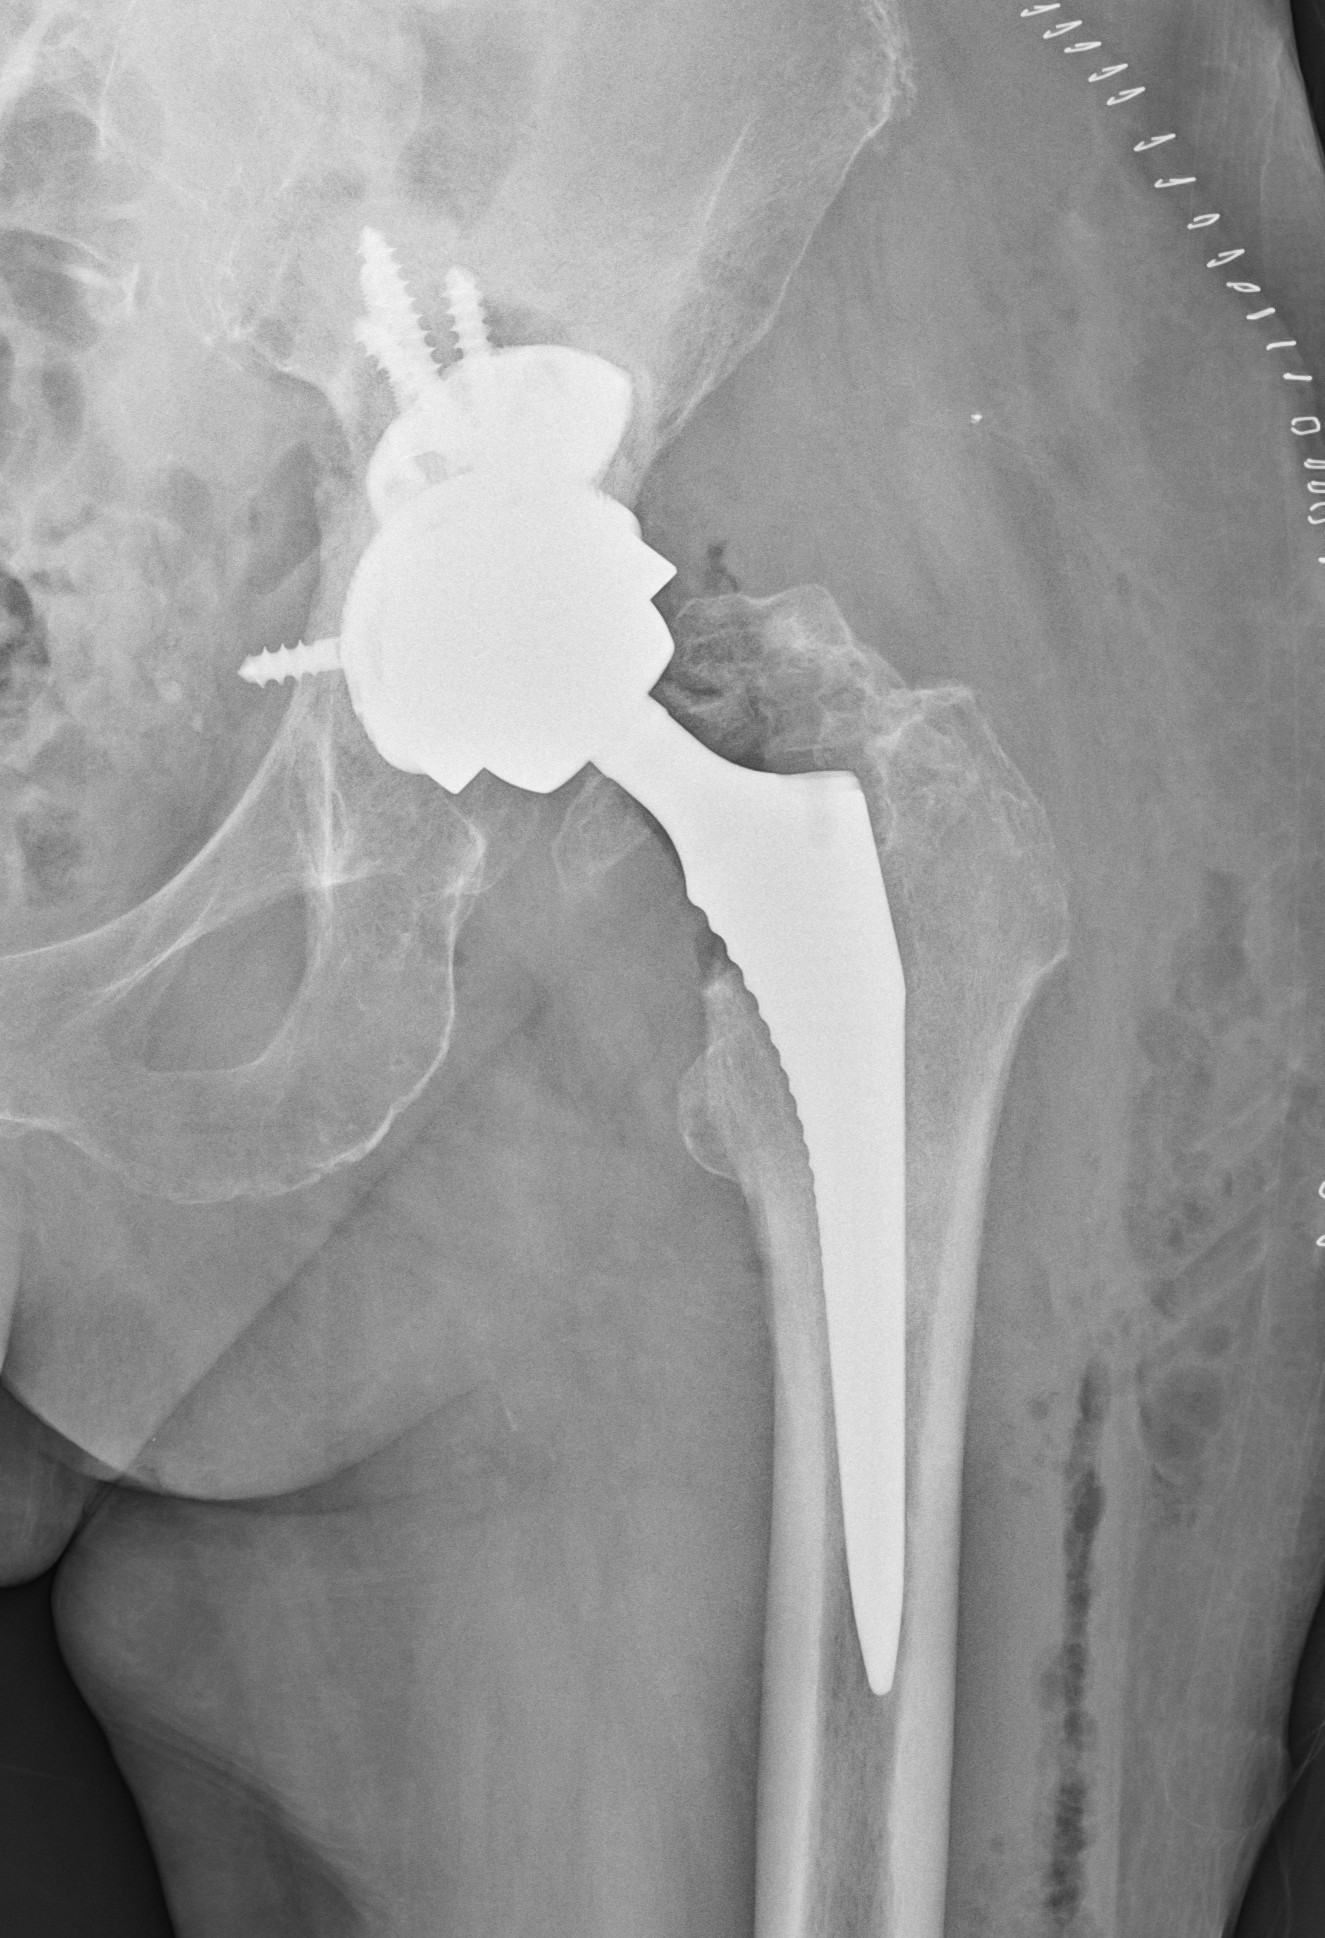

Tím II. ortopedicko – traumatologickej kliniky LF UK a UNB v Nemocnici sv. Cyrila a Metoda v Petržalke, pod vedením prednostu prof. MUDr. Borisa Šteňa, PhD. uskutočnil inovatívnu operáciu, počas revízie totálnej endoprotézy bedrového kĺbu. Inovácia spočíva v implantácii revízneho modulárneho komponentu.

Tento implantát novej generácie špeciálnych endoprotéz je určený pre operačnú liečbu zlyhaných endoprotéz pri rozsiahlych kostných defektoch. Išlo nielen o prvú operáciu na Slovensku, ale celkovo v poradí o štvrtú operáciu na svete s použitím tzv. „butress“ dlahy, vyrobenej z trabekulárneho titánu. Operácii sa úspešne podrobila 81 ročná pacientka s rozsiahlym kostným defektom v oblasti po implantácii jamky totálnej endoprotézy.

„S potešením môžem skonštatovať, že nám na pracovisku pri operačnej liečbe zlyhania totálnych umelých náhrad bedrových kĺbov pribudol inovatívny implantát. Máme tak k dispozícii viac možností na ošetrenie komplexných kostných defektov. Na rozdiel od predošlých implantátov, tieto vieme kombinovať ako čisto necementované alebo v kombinácii s kostným cementom a kostnými štepmi.“ uviedol Boris Šteňo, prednosta II. ortopedicko – traumatologickej kliniky LF UK a UNB. Rekonštrukcia veľkého kostného defektu na strane acetábula, teda v mieste implantácie jamky totálnej endoprotézy, býva vždy zložitá, niekedy žiaľ aj nemožná. Od tohto nového implantátu si naši odborníci sľubujú rozšírenie možnosti bezpečného použitia v revíznej endoprotetike, prípadne aj u pacientov po rozsiahlych kostných defektoch po zlomeninách panvy a acetábula.

Tento revízny systém implantátov je v súčasnosti dostupný iba v ôsmich krajinách Európy, v Nemecku, Rakúsku, Taliansku, Portugalsku, Španielsku, Veľkej Británii, v Poľsku a odteraz už aj na Slovensku. Špeciálny implantát je v týchto krajinách k dispozícii v 19 centrách, používať ho môže iba 23 vybraných operatérov. Na ortopedicko-traumatologickom pracovisku v petržalskej nemocnici bol špeciálny implantát v priebehu posledných 10 dní, využitý pri operáciách u ďalších troch pacientov.